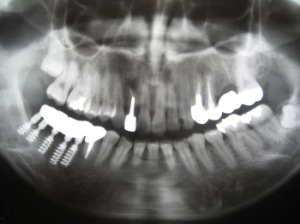

右下にインプラントを植立

1999/06/01